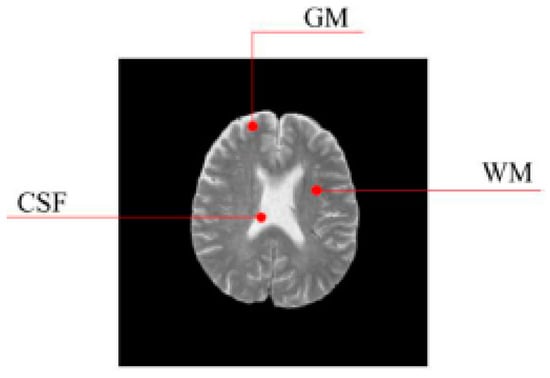

SBD: The database has DWI, T1 and T2 images of size 181 × 217 pixels. In our experiments, the classification results were quantified based on the ground truth of SBD. We added Rician noise to the analog image. In our experiments, the SNR (signal to noise ratio) values were set to 10 dB, 5 dB, 15 dB, and 20 dB, respectively. Shown in Figure 7, Figure 8, Figure 9 and Figure 10 are SBD images.

As shown in Figure 12, we greatly reduced the size of the input image by using three levels of wavelet decomposition. The approximation coefficient of level 3 is in the upper left corner of the image of the wavelet coefficient, and its size is only 16 × 16 = 256. To avoid boundary distortion, we calculate the boundary value by using the symmetric padding method [34].

Figure 7. SBD Images with SNR = 10 dB.

Entropy 20 00964 g007

Figure 8. SBD Images with SNR = 5 dB.

Entropy 20 00964 g008

Figure 9. SBD Images with SNR = 15 dB.

Entropy 20 00964 g009

Figure 10. SBD Images with SNR = 20 dB.

Entropy 20 00964 g010